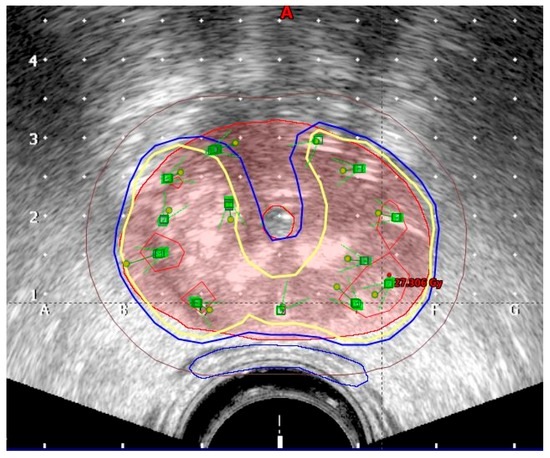

The planning target volume (PTV) was contoured by the radiation oncologist on each ultrasound slice and included the prostate with a 3 mm margin all around, except posteriorly, where no margin was given to avoid overdosing the anterior rectal wall. Superiorly, a margin of 5–7 mm was given to compensate for any post-implant edema and inadvertent caudal movement of the catheters in between the fractions. The PTV constraints were D90 (dose delivered to 90% of PTV) ≥ 97%, V95 ≥ 100%, and V150 ≤ 35%. Isodoses in transrectal ultrasound image are shown in Figure 1. A three-dimensional image with simulation of radiation is shown in Figure 2.

Figure 1. Isodoses in transrectal ultrasound image (red: 15 Gy; yellow: 9 Gy; blue: 8 Gy; brown: 5 Gy).